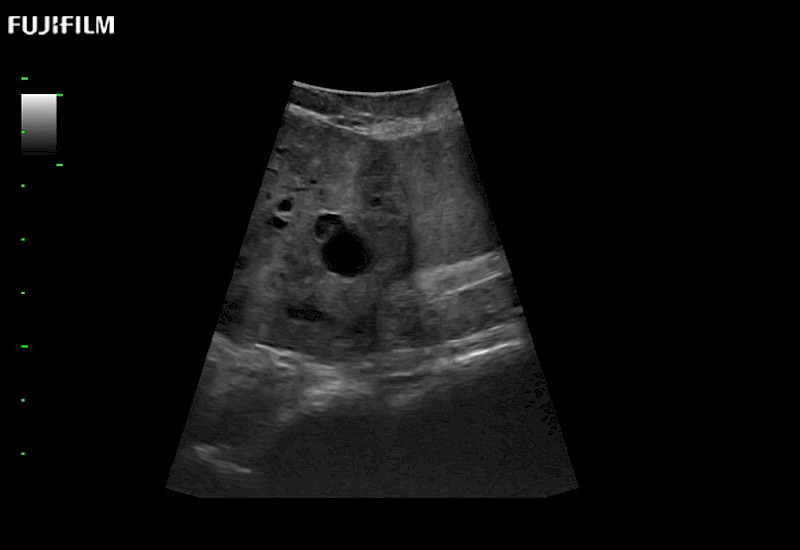

Extraordinary high-resolution digital imaging

- Exceptional near and far-field resolution

- Instant feedback on tumor margin delineation

- Valuable information to guide tumor resections

- Exceptional near and far-field resolution

- Instant feedback on tumor margin delineation

- Exceptional near and far field resolution

- Instant feedback on tumor margin delineation

- Valuable information to guide tumor resections

The ARIETTA 750 incorporates all of the proven technologies and functions that medical professionals have come to expect from Fujifilm Healthcare.

ARIETTA 750 is the definitive diagnostic ultrasound solution for any clinical setting - Private Office, Imaging Center, or Hospital. The ARIETTA platform provides the ultimate in clinical performance with its state-of-the-art features and large user-friendly display.

The ARIETTA 650 DI combines trusted Fujifilm Healthcare technologies and features tailored for surgical oncology.

Designed to meet the demands of surgeons, the ARIETTA 650 DI offers precise guidance. Its advanced capabilities and large, intuitive display offer accurate and efficient care in operating rooms and specialized surgical settings.